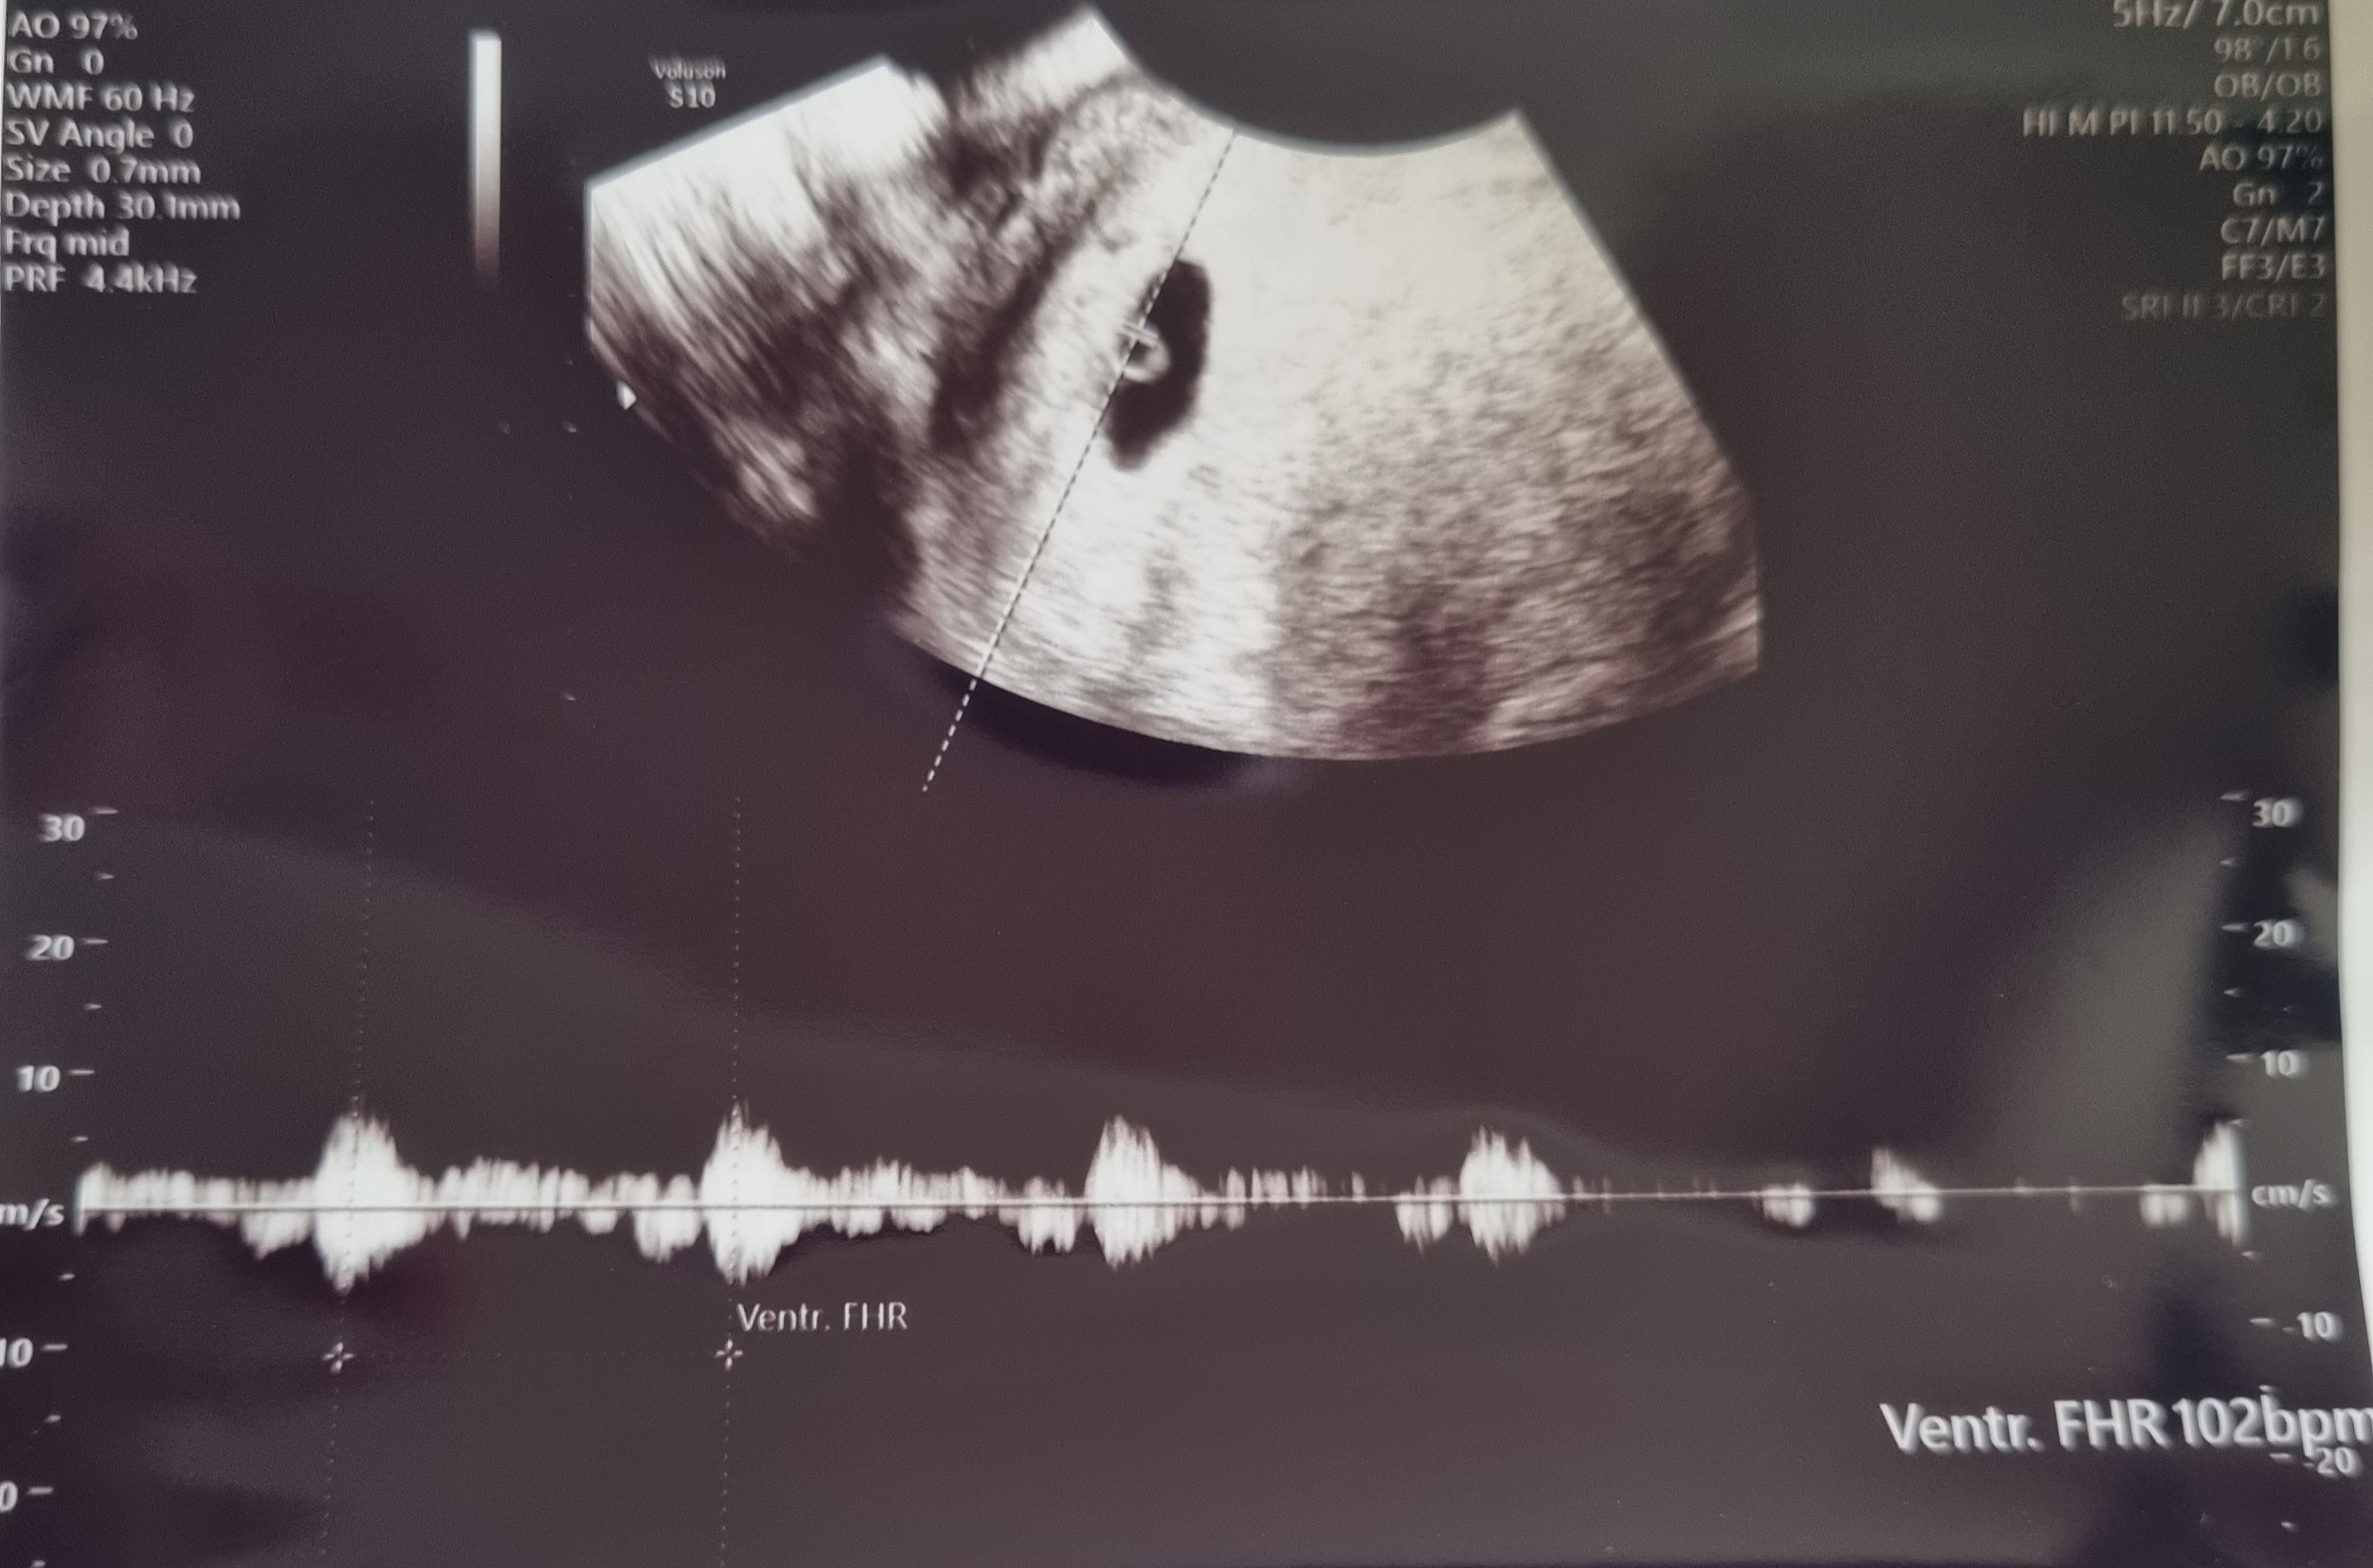

짜잔!

아기집과 난황? 이 잘 생겼는지

진짜 임신이 맞는지만 확인해도 감사할 일이었는데

심장소리까지 확인했습니다!!!

정말정말 작은게 반짝반짝 거리더라구요

그게 심장이라며...😭😭

심장소리듣는데 사실 울컥했어요

신기한데..울컥하고.. 뭔가 설명할 수 없는 기분

내가 정말 임신했구나..를 실감한 순간이었어요

붙여주신 초음파 사진들!

보통 '다이아몬드반지' 초음파라고 하더라구요?! ㅎㅎ

듣고보니 정말 다이아반지처럼 난황? 부분이 반짝반짝 거려서 그런가봐요💍